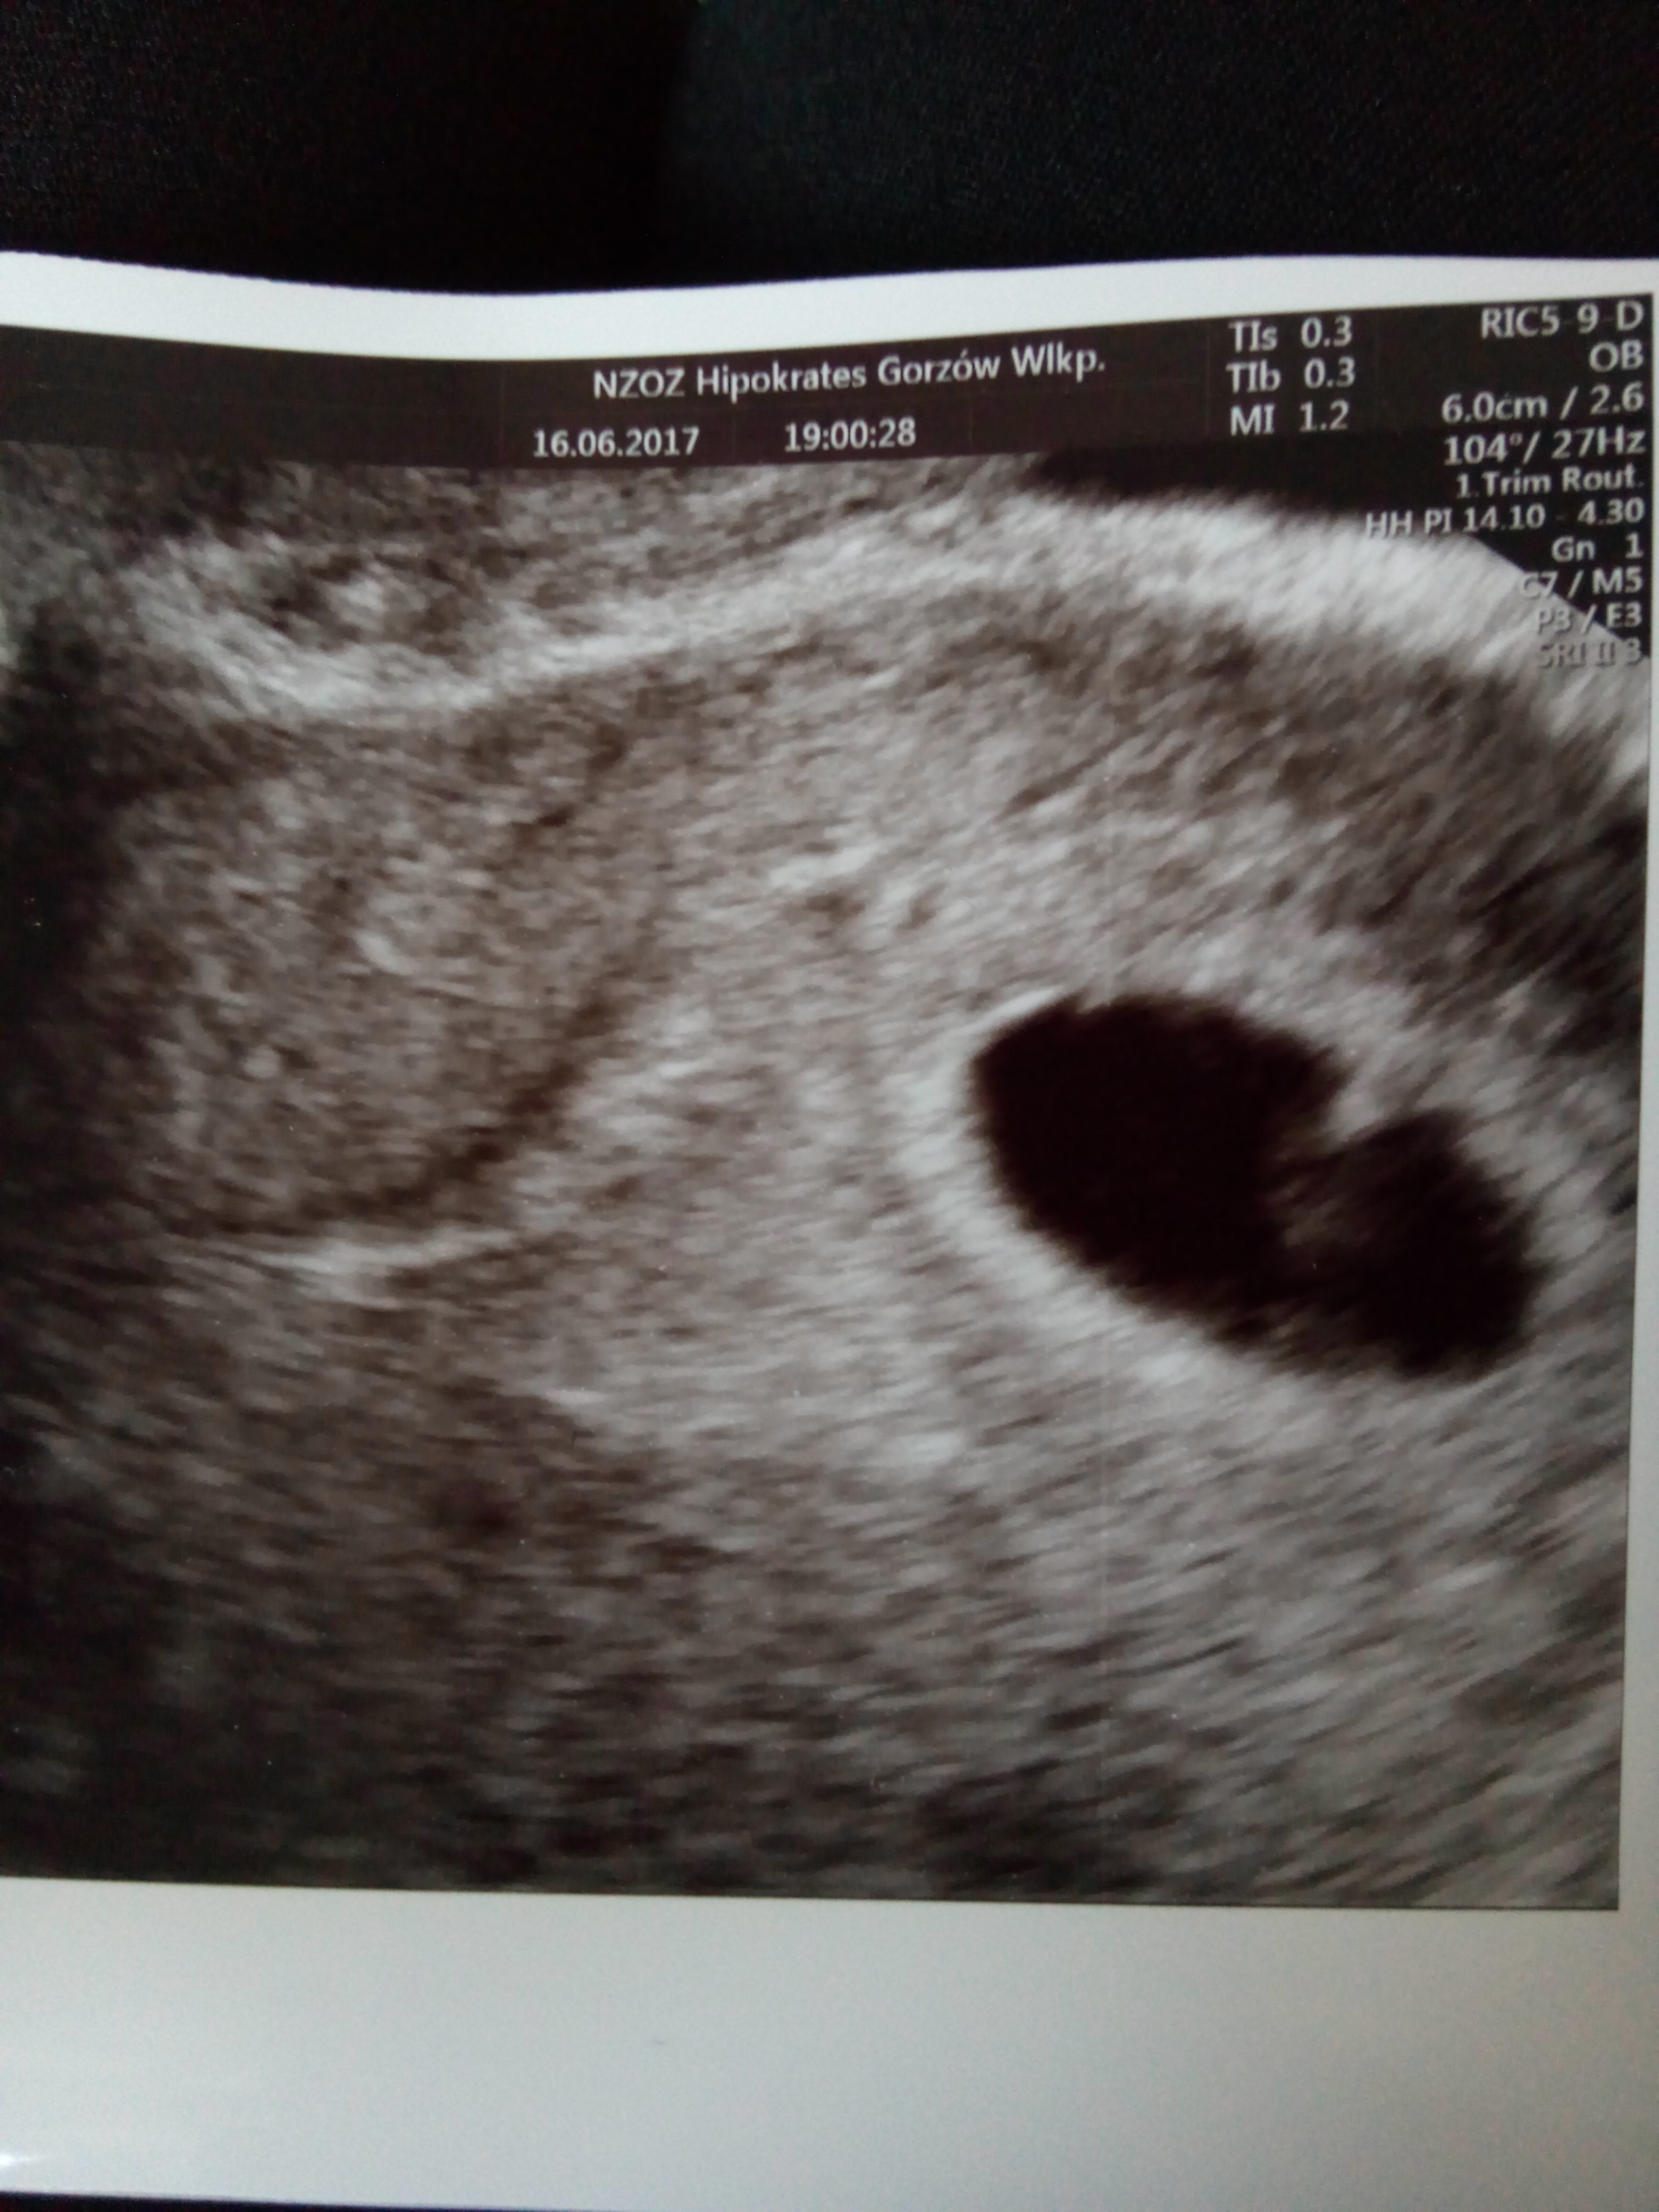

Dziewczyny ja juz po wizycie jest dzidzia i serduszko bije jak dzwon ;)

Załączniki

• IMG_20170616_201745.jpg

IMG_20170616_201745.jpg

777,3 KB · Wyświetleń: 134